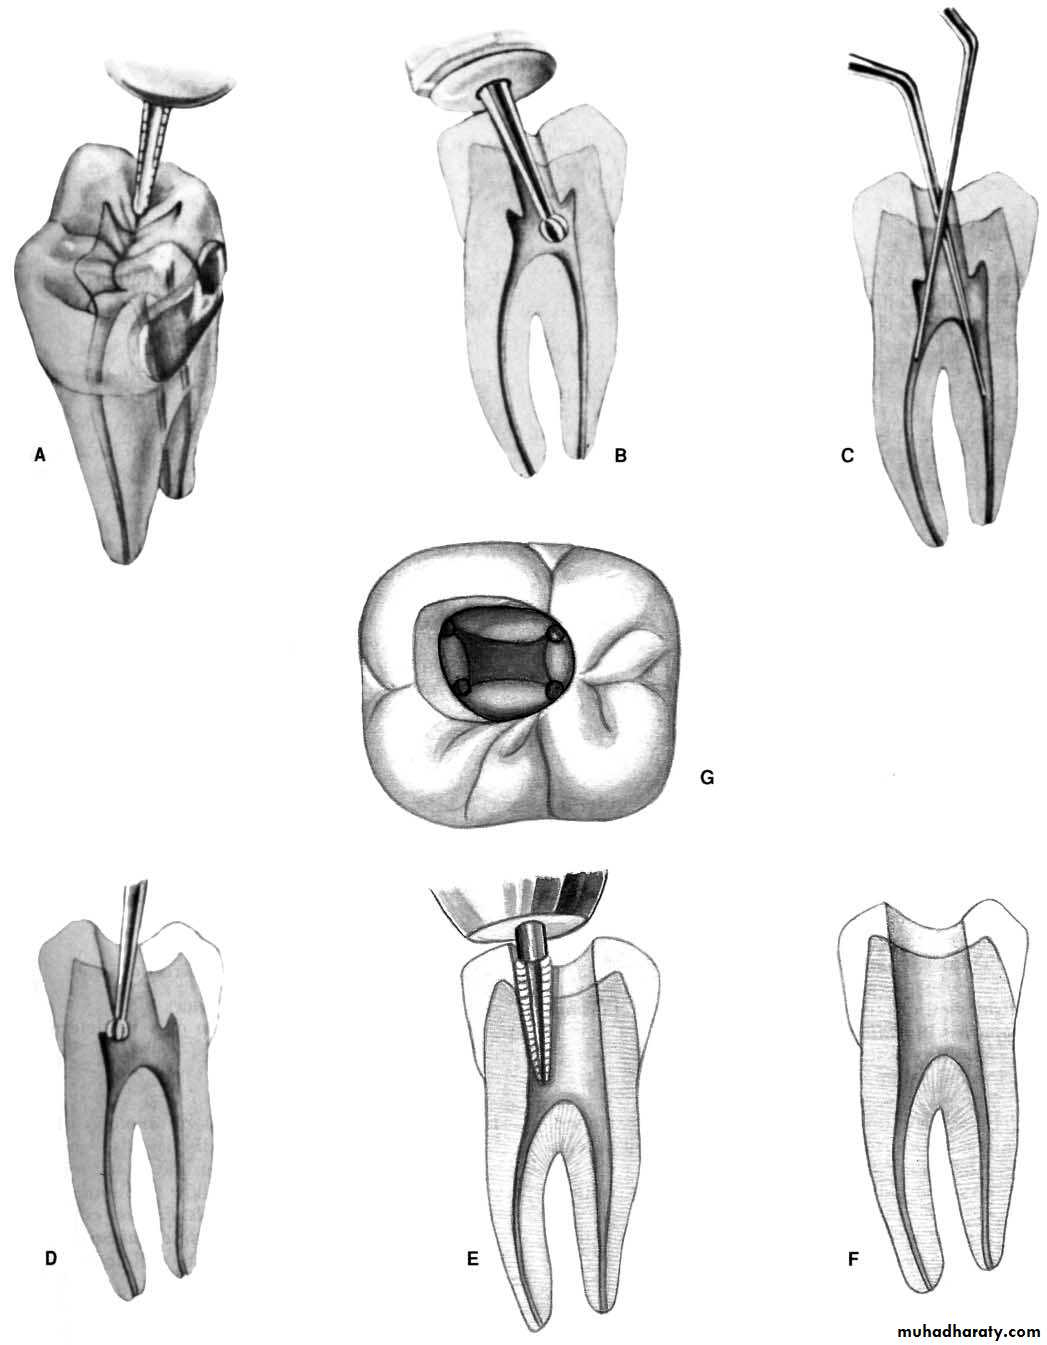

A, Initial access penetration occurs in the middle of the incisal-cervical dimension.

B, After locating the canal, the clinician extends the access incisally.

Error in access opening in max. ant teethA.PERFORATION: at the labiocervical caused by failure to complete convenience extension toward the incisal, prior to the entrance of the shaft of the bur.B.GOUGING: of the labial wall caused by failure torecognize the 29-degree lingual-axial angulation of the tooth.

C. GOUGING: of the distal wall caused by failure to recognize the 16-degree mesial-axial inclination of the tooth. D.PEAR-SHAPED PREPARATION: of the apical canal caused by failure to complete convenience extensions. The shaft of the instrument rides on the cavity margin and lingual “shoulder.” Inadequate débridement and obturation ensure failure.

E.DISCOLORATION: of the crown caused by failure to remove pulp debris. The access cavity is too far to the gingival with no incisal extension.F. LEDGE: formation at the apical-distal curve caused by using an uncurved instrument too large for the canal. The cavity is adequate.

G.PERFORATION: at the apical-distal curve caused by using too large an instrument through an inadequate preparation placed too far gingivally. H.LEDGE: formation at the apical-labial curve caused by failure to complete the convenience extension. The shaft of the instrument rides on the cavity margin and “shoulder.”

Error in access opening in man. ant. teeth

A.GOUGING: at the labiocervical caused by failure to complete convenience extension toward the incisal prior to entrance of the shaft of the bur. B.GOUGING: of the labial wall caused by failure to recognize the 20-degree lingual-axial angulation of the tooth.

C.GOUGING: of the distal wall caused by failure to recognize the 17-degree mesial-axial angulation of the tooth.D.FAILURE to explore: débride, or fill the second canal caused by inadequate incisogingival extension of the access cavity.

E. DISCOLORATION: of the crown caused by failure to remove pulp debris. The access cavity is too far to the gingival with no incisal extension. F.LEDGE: formation caused by complete loss of control of the instrument passing through the access cavity prepared in proximal restoration.